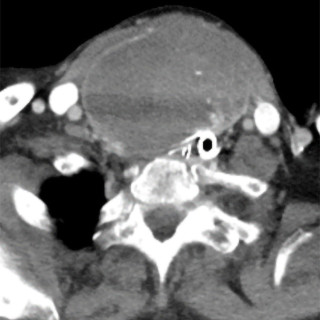

CT-bildene er fra en undersøkelse med opptak uten intravenøs kontrast. Bildet til venstre viser høy attenuasjon i myokard i venstre ventrikkel, og i mindre grad i høyre ventrikkel. Attenuasjonen er tilnærmet lik skjelett i bildet, og tettheten kan passe med forkalkninger. Opptaket er gjort på en spektral-CT, som har økt mulighet for å differensiere mellom ulike vevstyper. Maskinen utnytter de ulike energinivåene i røntgenstrålen, og den kan skille mellom grunnstoffer som jod og kalk utfra absorpsjonsnivået, da begge gir høy attenuasjon. Kalksuppresjon, vist på bildet til høyre (B), bekrefter...